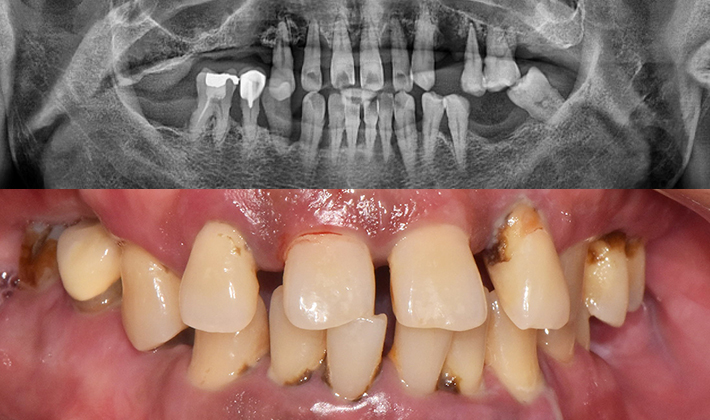

치과가 무서워 10년 동안 미뤄온 임플란트 수술 그 결과는?

2026.01.21